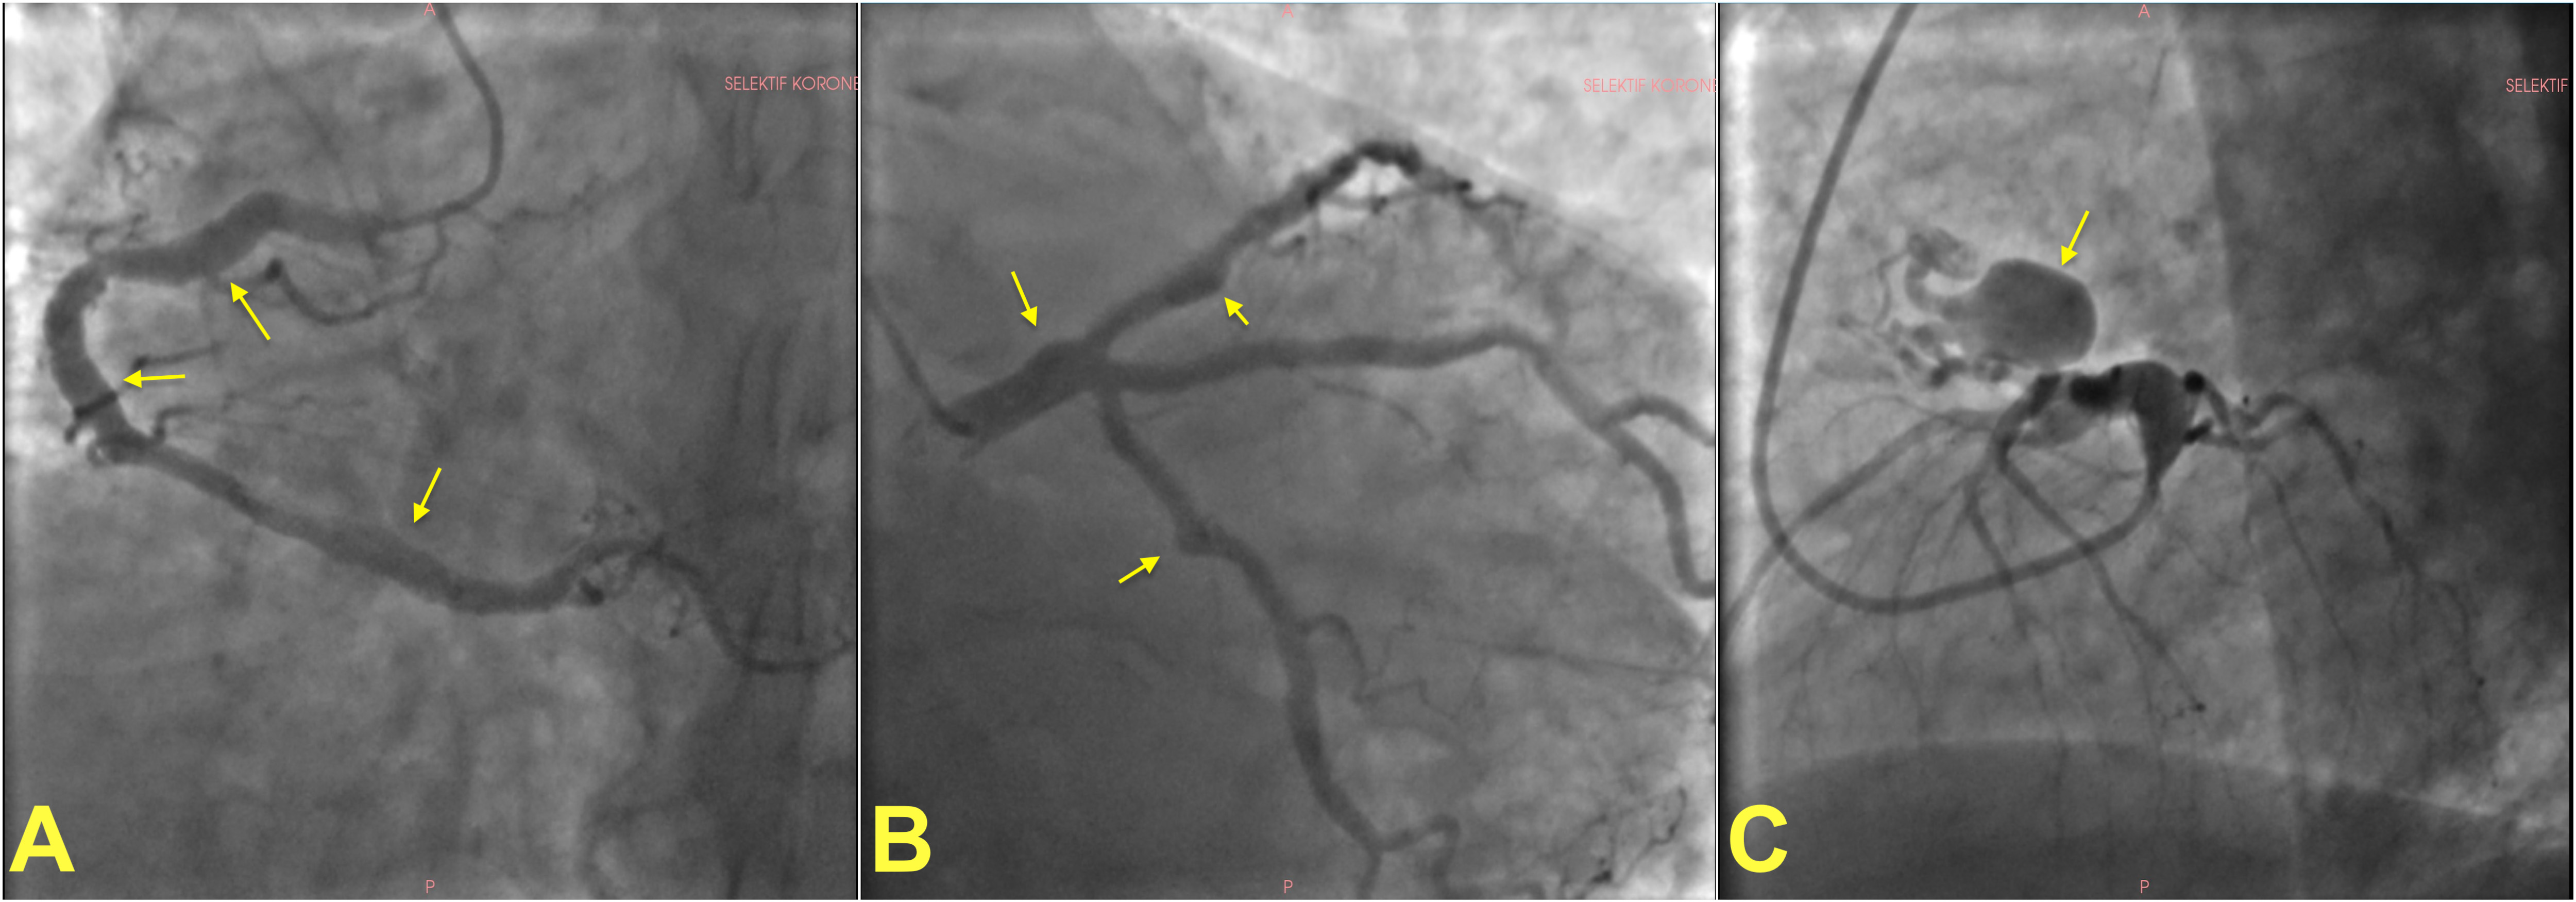

Fig. 1.

Fig. 1.

Invasive angiographic images showing examples of coronary artery ectasia and aneurysms. (A) shows multiple fusiform atherosclerotic coronary artery aneurysms on the right coronary artery in a patient. Left coronary angiogram of the same patient showing multiple coronary aneurysms on the left main stem, left circumflex and left anterior descending artery (B). A giant saccular aneurysm in a different patient (C). Arrows show aneurysms in all panels.